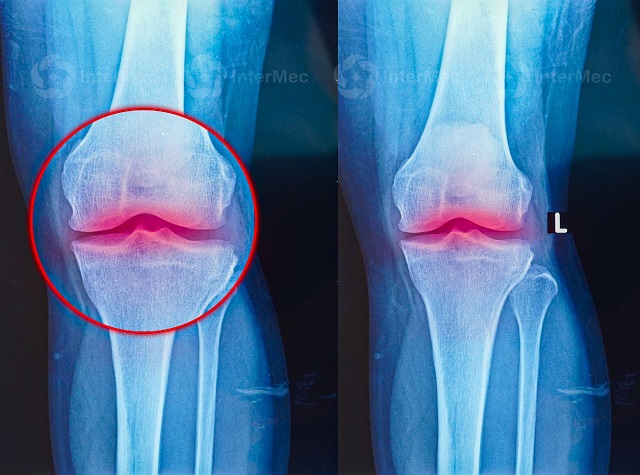

1. Thoái hóa khớp gối

- Là bệnh phổ biến nhất ở người lớn tuổi, xảy ra khi sụn khớp bị bào mòn do lão hóa, chấn thương hoặc vận động quá sức.

- Ảnh hưởng: Thoái hóa khớp gối gây đau nhức, cứng khớp, hạn chế vận động, giảm chất lượng cuộc sống. Nếu không điều trị, bệnh có thể dẫn đến biến dạng khớp, mất chức năng vận động, tăng nguy cơ té ngã, gãy xương và tàn phế.